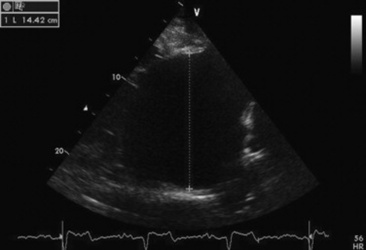

Echocardiograms should also be performed from the left cardiac window when the entire heart cannot be successfully imaged from the right side; atrial fibrillation is present; abnormalities of the mitral valve, aortic valve, pulmonic valve, aorta, pulmonary artery, left atrium, left ventricle, or outflow portion of the interventricular septum are detected; or murmurs originating from the mitral, aortic, or pulmonic valves are detected or a pericardiocentesis is planned. The maximal diameter of the left atrium should be obtained from the left cardiac window at the level of the left coronary artery, parallel to the mitral valve (Fig. 30-3). The diameters of the aorta and pulmonary artery should be measured from similar locations in the vessel on the two-dimensional echocardiogram and compared. Echocardiography should be considered a useful diagnostic test to evaluate patients with the following complaints, physical examination findings, or tentative diagnoses:

image

Fig. 30-3 Two-dimensional echocardiographic image of the left atrial diameter obtained from the left parasternal long axis window in a horse with mild left atrial enlargement secondary to cardiomyopathy and mitral regurgitation.